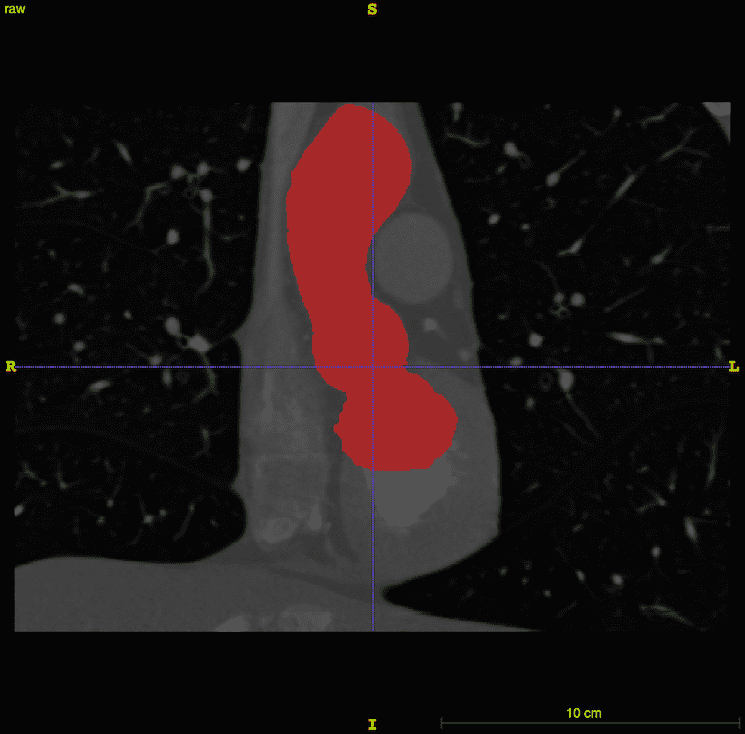

The aortic root and ascending aorta were segmented by a semi-automated method implemented in the ITK-SNAP software. ITK-SNAP [43, 44], which is based on the Insight Segmentation and Registration Toolkit (ITK) [45, 46], provides a graphical interface for the implementation of the active contour model, also known as Kass snakes [47], for semi-automatic segmentation. The algorithm works by minimizing an energy functional that is determined by voxel intensities. The generated segmentation is shown in Fig. 2.

A three-dimensional representation of the aortic root and ascending aorta was generated from publicly available medical image data. This study uses one of the sample data sets from the OsiriX DICOM Image Library that consists of three-dimensional computed tomography angiography (CTA) of an anonymous patient’s chest following administration of a contrast agent. The use of a contrast agent enables better discrimination of the blood vessels and heart chambers than non-contrast CT images. The image data were acquired at the Ronald Reagan University of California at Los Angeles Medical Center in Santa Monica, CA using a Siemens SOMATOM Sensation 16 CT scanner. The image resolution is 512512355 with a voxel size of 0.470.470.5 mm. The image was processed by an anisotropic diffusion filter to mitigate noise. Sample renderings of the patient data are shown in Fig. 1.

Several distinct software applications are used to construct the full model. The construction pipeline starts with three-dimensional NRRD (nearly raw raster data) files containing the medical image data. Segmentation and initial geometry construction is generated using ITK-SNAP. Further adjustments are made in SOLIDWORKS (Dassault Systèmes SOLIDWORKS Corporation, Waltham, MA, USA) to fix any irregularities. SOLIDWORKS is also used to generate the geometry of the aortic valve leaflets. The STL (STereoLithography) geometry constructed in SOLIDWORKS is then used in Bolt (Computational Simulation Software, LLC, American Fork, UT, USA) to construct a hexahedral mesh for the aortic root. Placement of the model valve leaflets within the aortic root is finalized in Trelis (Computational Simulation Software, LLC, American Fork, UT, USA), which is a mesh generation software application based on CUBIT from Sandia National Laboratory. Trelis is also used to generate tetrahedral meshes of the aortic valve leaflets. Because the leaflets and vessel wall are both modeled using the IB method, it is not necessary to use conforming discretizations of the leaflets and wall, which greatly simplifies the mesh generation process. The overall model construction workflow is detailed in Algorithm 1. The inflow section of the model is truncated at the left ventricular outflow tract, and the outflow section of the model is truncated in the aortic arch before the first bifurcation. In the FSI simulation, the inflow and outflow sections are coupled to reduced-order models that provide driving and loading conditions, and that establish realistic pressure differences across the model vessel.